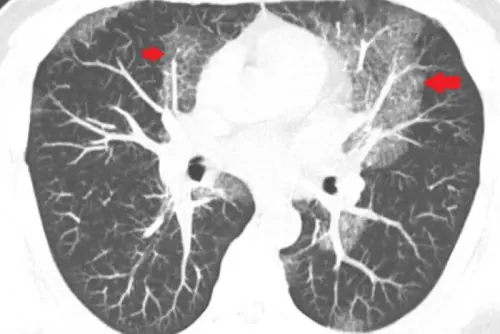

▲▼魏先生胸部影像檢查有大片白影,診斷結果卻非肺炎,而是「蛋白質沉積症」。(圖/台北慈院提供)

台北慈濟醫院胸腔內科主任藍冑進表示,魏先生從事搬運工作多年,體能良好,近2年卻常出現喘不過氣、背痛症狀,甚至在搬重物時差點窒息,經檢查,發現他的肺部有大片白影,起初懷疑為慢性發炎,但細菌、黴菌檢查均為陰性,3個月後白影惡化,故進行肺部穿刺切片,這才確診為蛋白質沉積症,所幸經全肺灌洗術治療後,在術後第3天即康復出院。

藍冑進指出,蛋白質沉積症的發生率僅百萬分之一,病因可能與自體免疫異常有關;一般狀況下,肺泡會分泌蛋白質以助維持張開與氣體交換,但若異常累積、無法清除,將堵塞肺泡,引起缺氧及呼吸困難,嚴重甚至危及生命。由於初期症狀不明顯,常與肺炎、肺纖維化混淆,增加延誤診斷風險。